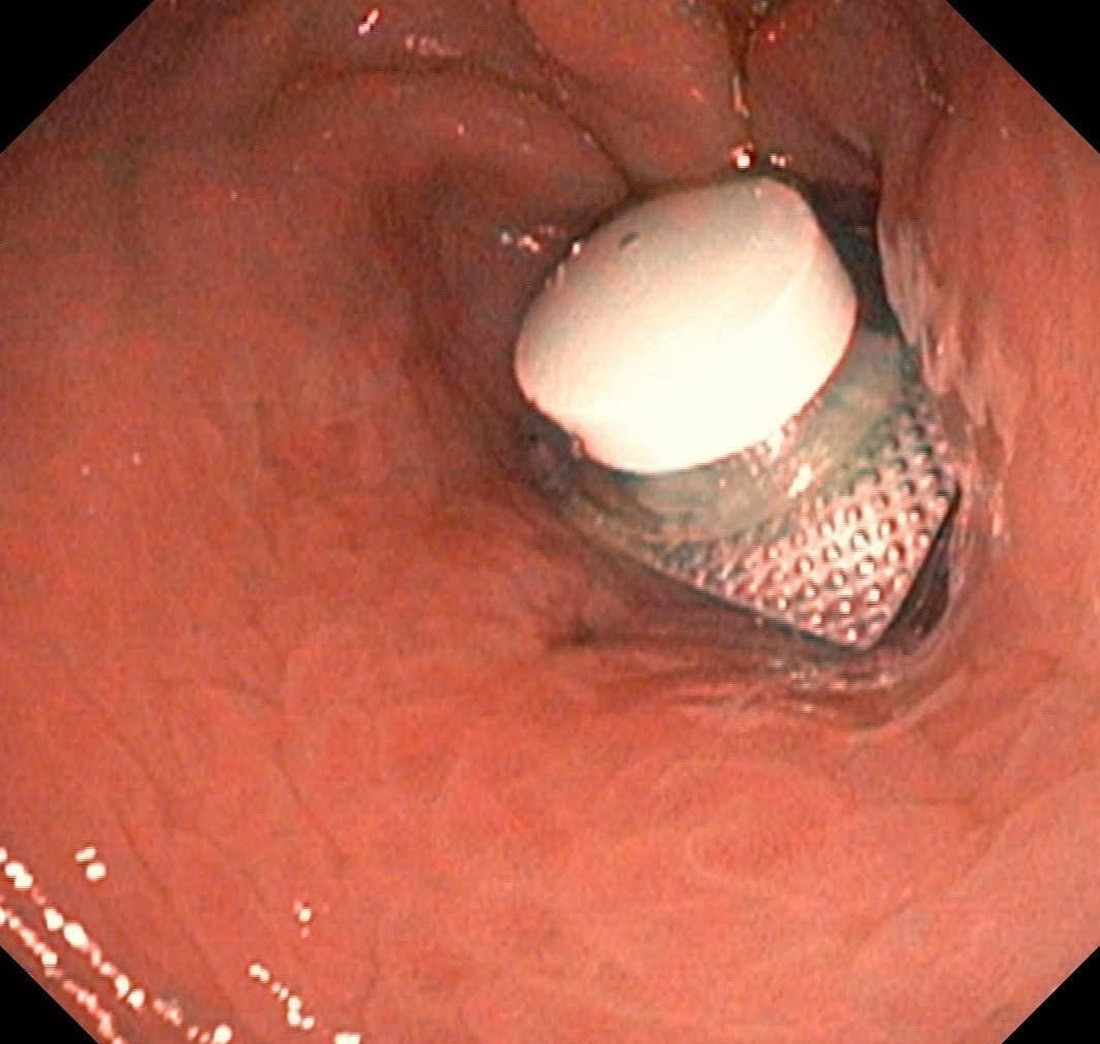

Viên thuốc còn nguyên vỏ được phát hiện tại vị trí cuối dạ dày của bệnh nhân. Ảnh: Bệnh viện cung cấp

Trước đó, bệnh nhân nam 52 tuổi nhập viện cấp cứu trong tình trạng đau bụng dữ dội. Qua thăm khám lâm sàng, bệnh nhân được bác sĩ chỉ định nội soi dạ dày và phát hiện tại môn vị có dị vật là viên thuốc còn nguyên vỏ, gây trầy xước niêm mạc dạ dày.